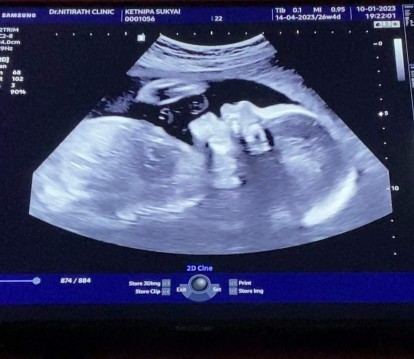

อัลตราซาวด์ครั้งที่ 2 ค่ะ ชัดเจน รู้เพศกันไปเลย แม่ๆเดาว่าญ.หรือช.กันบ้างคะ 😆😆

อัลตราซาวด์